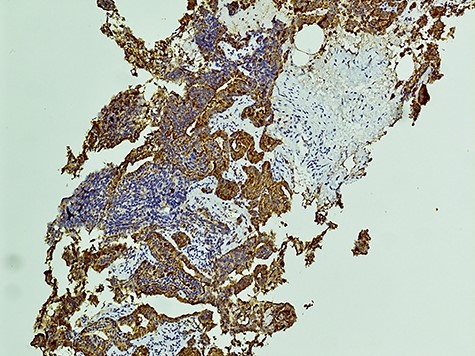

Histology from trans-rectal ultrasound (TRUS) biopsy of the prostate showed a conventional microacinar type prostatic adenocarcinoma of Gleason score 4 + 4 = 8 with an intermingled component of SCC, composed of cohesive sheets of small cells with scant cytoplasm, hyperchromatic nuclei and nuclear molding with increased mitotic activity (Fig. 2). The cytomorphology was similar to the neck FNA. The small cell component showed positive staining for neuroendocrine markers Synaptophysin and CD56. The Ki-67 index was 70%. PSA showed scattered positivity. Overall, the features were consistent with a mixed microacinar adenocarcinoma and SCC. Following the diagnosis from TRUS biopsy, PSA immunostain was carried out on the FNA material, which showed scattered positivity.

The diagnosis of SCCP is based on morphological features defined in the World Health Organization (WHO) classification criteria of pulmonary neoplasms (WHO 2015). From a diagnostic point of view, it is important to recognize this rare variant and not misdiagnose it for a high-grade Gleason 5 pattern, as there is a morphological overlap [5]. In cases where there is morphologic concern for neuroendocrine carcinoma (sheet-like architecture, nuclear molding and scant cytoplasm), it is essential to perform immunohistochemistry with neuroendocrine markers and PSA. In our case, the SCC component was strongly positive for neuroendocrine markers Synaptophysin and CD56 with focal positivity for PSA. In the conventional component it was the reverse; strong PSA positive and very focal NE scattered cells (Figs 3 and 4). This is in line with the literature findings [5, 8].